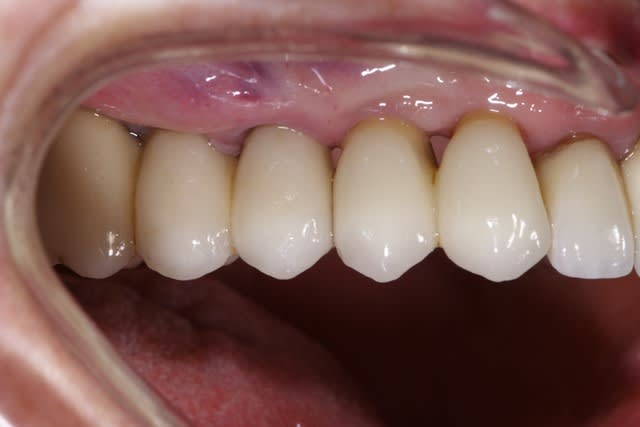

Bon alors revenons a cette 15.

On voit bien sur l'historique radio que la migration apicale a débuté entre janvier et mai 2014. Date à laquelle j'ai dû changer la 14.

J'aime bien les points de contacts assez serrés et là j'ai le souvenir qu'il était très costaud.

Je pense donc que la migration est dû a une compression de la 15 par effet de coin comme la supputer Shadow.

De toute manière maintenant elle ne bougera plus!